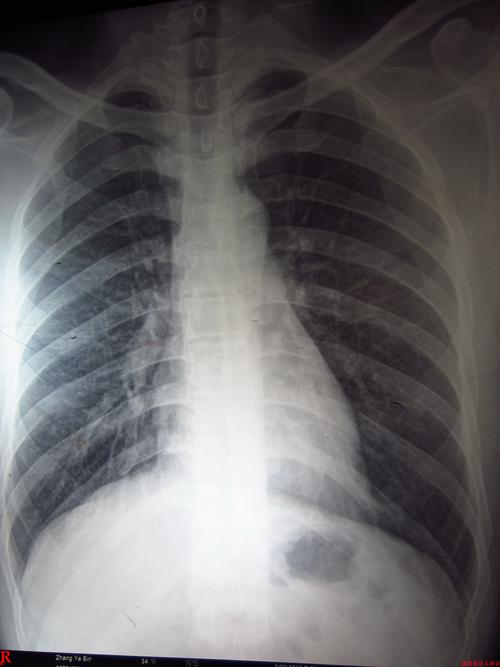

肺部图片胸片,胸片图片肺大泡

这张胸片肺部有问题吗?

胸片图片肺大泡

肺部胸片

胸片图片

肺部图片

肺炎胸片